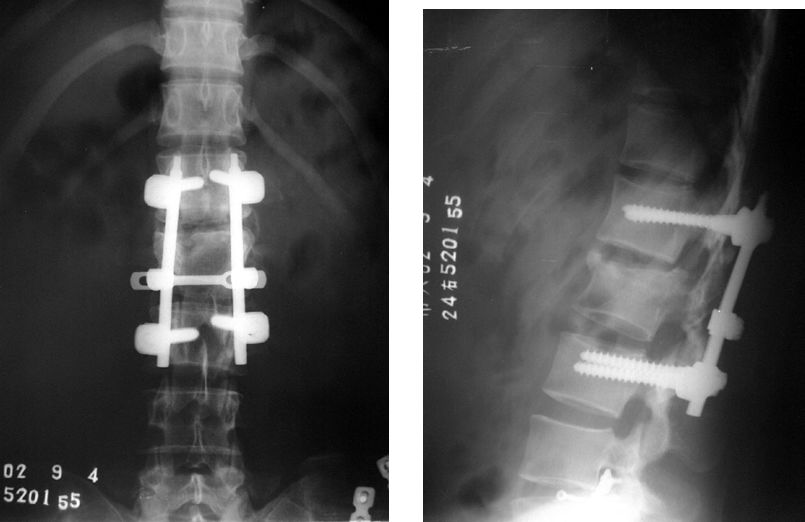

Si tout le corps est stable, la fracture déplacée doit être opérée immédiatement en cas de symptômes neurologiques.